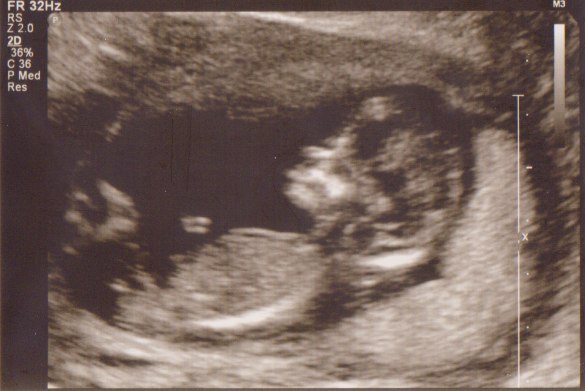

Vi fik med det samme øje på den lille guldklump som lå og hyggede sig gevaldigt inde i sin babyhule - h*n kunne slet ikke ligge stille, så det tog lidt tid inden hun fik målt nakkefolden, men i mellemtiden viste hun os hjernehalvdelene, mavesækken, næsebenet, alle 5 fingre på den ene hånd - kan næsten ikke huske alt det hun viste os - det var bare så fantastisk

Hun satte mig 2 dage frem, så jeg i dag er 13+3 og har termin den 23. september